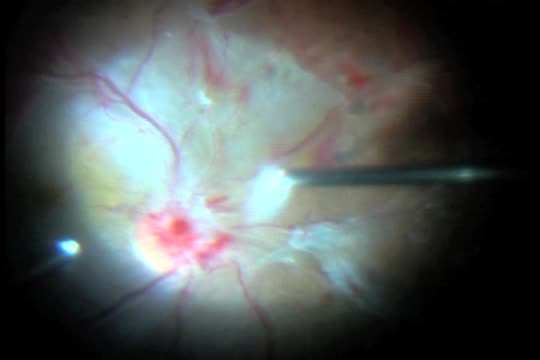

New Technique for Diabetic Dissection

Maria H. Berrocal, MD